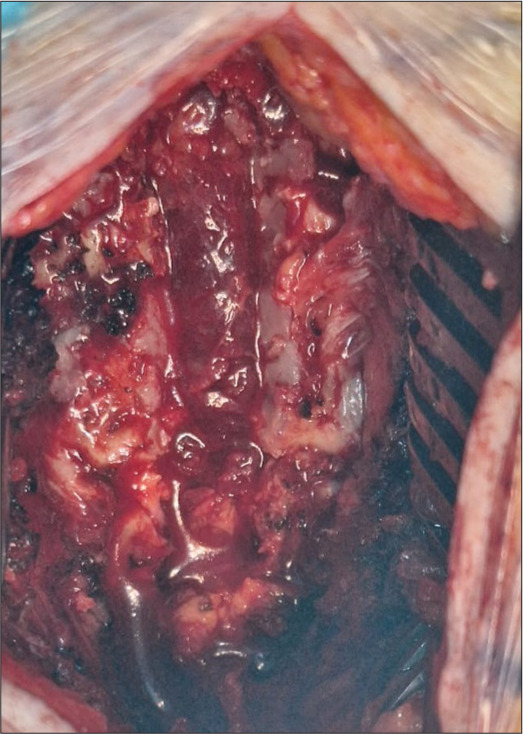

Case description: A 70-year-old male presented with 3 months of progressive paraparesis. The magnetic resonance showed a compressive epidural T3-T5 lesion that was successfully removed. The lesion proved histopathologically to be a benign cavernous angioma.